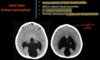

OBSTRUTIVE HYDROCEPHALUS

AQUEDUCTAL STENOSIS:

-acquired causes?

Extrinsic compression

tectal plate glioma / pineal tumour / posterior fossa tumour / cerebral vascular malformation

Intrinsic stenosis

infection: meningitis/ventriculitis

subarachnoid haemorrhage (SAH)